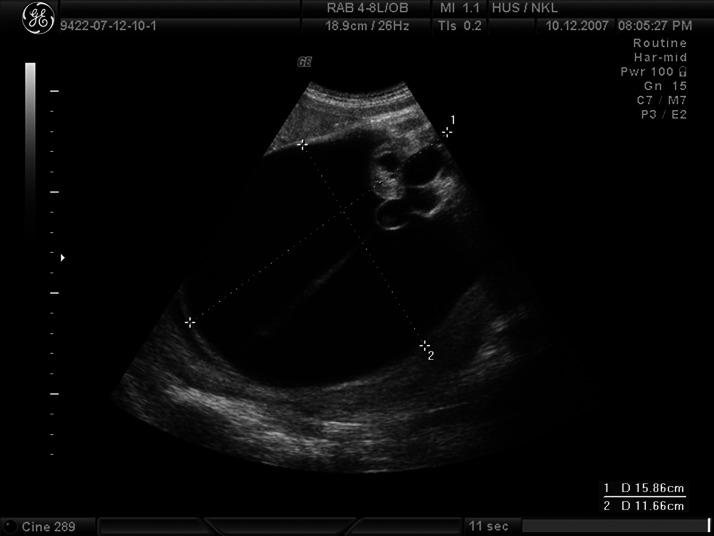

Fetal sacrococcygeal teratoma (SCT) is the most common tumor in the neonatal period and is easily detected by modern ultrasound techniques, mostly during the second-trimester screening. It can cause significant fetal/neonatal morbidity and mortality due to its size, vascular loading, possible rupture, and labor dystocia. Mostly cystic teratomas have favorable prognosis, but if untreated in utero, they may rupture or cause labor obstruction. Cesarean delivery, especially with the vertical incision, increases significantly maternal morbidity due to the hemorrhage and the risk of the uterine rupture in the subsequent pregnancies. The authors report in details two SCT cases with uncomplicated vaginal delivery after peripartum ultrasound-guided drainage of the cystic teratoma. We conclude that the percutaneous emptying of the cystic SCT is an easy, encouraging, safe, and efficient procedure and enables normal vaginal delivery, thus avoiding labor dystocia and possible complications of the cesarean delivery and the risk of tumor rupture.